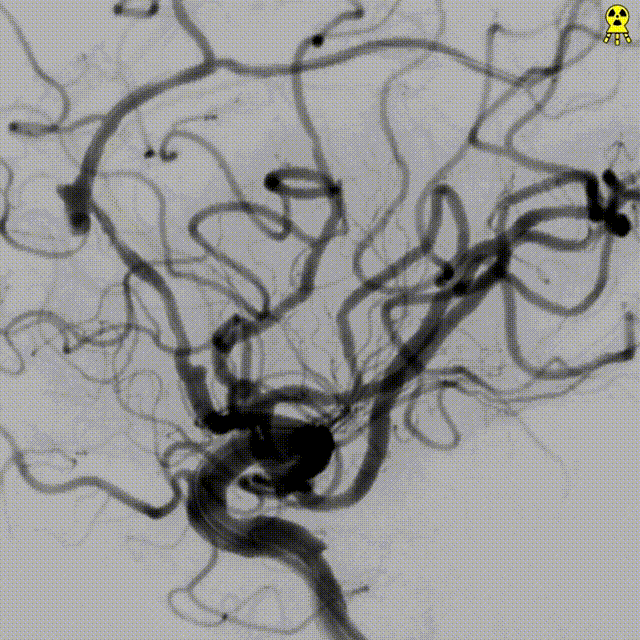

DSA:提示左侧大脑前动脉A2段动脉瘤,其他血管造影未见明显异常。

术前诊断:左侧大脑前动脉A2段动脉瘤。

治疗方案:血流导向装置植入。

支架到位,远端打开(工作位):支架释放过程中,轻柔推送支架系统,支架释放,打开良好。

术后造影:支架覆盖夹层动脉瘤,贴壁良好。

术后造影:

强易达(Choydar)血流导向密网支架术中操作顺利,支架推送及释放过程平顺,未见管壁损伤,支架喇叭口形状设计贴壁效果好;径向支撑力高。